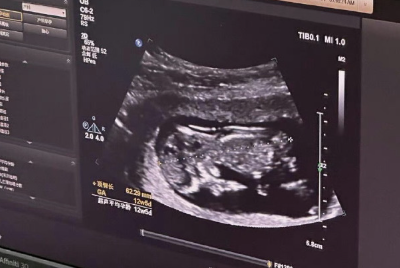

女性检查项目:包括妇科常规检查、B超(评估卵巢和子宫状况)、内分泌激素水平检测、AMH(卵巢储备功能评估)、染色体核型分析、传染病筛查(乙肝、丙肝、梅毒、艾滋病等)、TCT和HPV筛查、心电图、凝血功能等。

卵泡监测:在促排卵期间,医生会通过B超和抽血(监测激素水平)来实时跟踪卵泡的生长发育情况,以便及时调整用药。